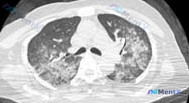

整理了一份胸部CT影像分析病例,影像核心表现: 1. 单侧(右肺)大范围弥漫性密度增高影,混合斑片状磨玻璃影与实变影 2. 可见支气管充气征,肺体积无明显改变 3. 病变区可见细网格影+小叶间隔增厚,呈铺路石样改变 4. 左肺未见明显异常,胸膜、胸壁结构正常 目前没有提供完整的临床病史和实验室结果,...

整理了一份胸部CT的影像分析资料,先不看病史,只看影像表现,大家第一眼会先往哪个方向走? 主要影像发现: - 肺窗横断面,双肺下叶背侧、胸膜下区域 - 对称性片状磨玻璃影(GGO),伴网格状影及小叶间隔增厚 - 典型「铺路石征」改变 - 未见明显支气管充气征,无胸腔积液或胸膜增厚 原分析首先提了心源...

整理到一个病例资料,大家来讨论一下: 37岁女性,有肾移植史。1周前开始出现咳嗽、发热、疲劳。过去病史包括静脉注射毒品、20多岁的商业性行为,1个月前去过马来西亚。 查体:体温38.3℃,血压114/64mmHg,心率110次/分,呼吸19次/分,氧饱和度93%(室内空气),双肺呼吸音粗。 化验:血...